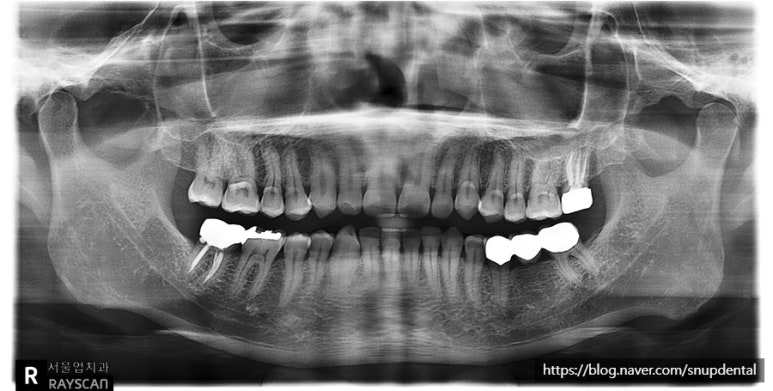

왼쪽 아래 브릿지 치아가 불편하다고 서울업치과에 내원하신 환자입니다

불편한 증상을 확인하고 어금니(#37) 부위에 문제가 있고, 작은 어금니(#35)는 살려 쓸 수 있다고 판단됩니다.